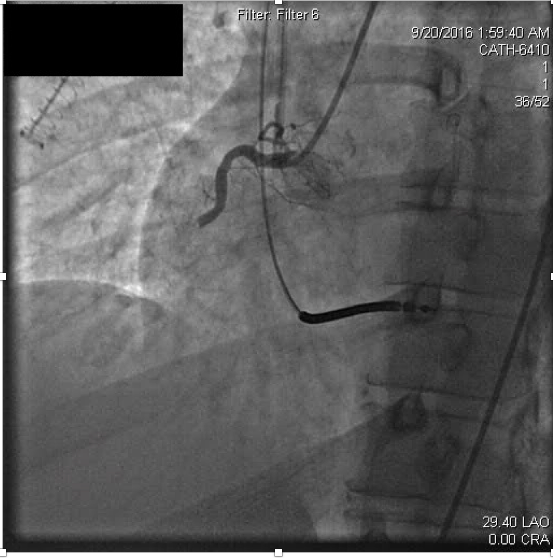

Myocardial infarctionin patients under the age of 45 is considered rare occurring in approximately 6-10% of the general population. In many cases, premature coronary atherosclerosis plays an important causative role, however about 20% of young adult coronary thrombosis can be attributed to hypercoagulability. In this article, we present a 43 year old patient with recurrent coronary thrombosis. While an initial presentation of acute myocardial infarction appeared driven by common re-thrombosis and acute stent thrombosis revealed a hypercoagulable state. This case highlights challenges in management of acute myocardial infarction and hypercoagulable states. It emphasizes the vigilance that must be exercised in generating differential diagnoses for coronary thrombosis.References